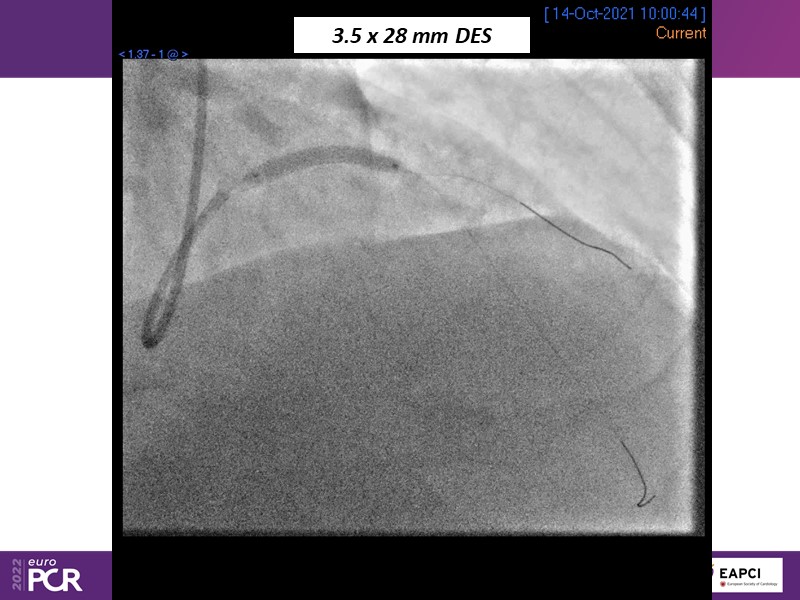

Alexandre Abizaid, Marco Valgimigli, Fazila Malik, Luca Testa, Patrick W. Serruys, Damiano Regazzoli, Kumar Prathap, and Sandeep Basavarajaiah take turns in this session to discuss two innovative technologies: a stent platform with nanotechnology and a novel drug-coated balloon (DCB). These novel technologies both have unique features that could change daily practice and improve outcomes.

- To understand how useful is a DES and DCB stent platform in complex coronary artery disease settings with case demonstrations and follow-up in diabetes mellitus

- To look at the technology behind the products, what the key data suggest and important takeaways from case permutations